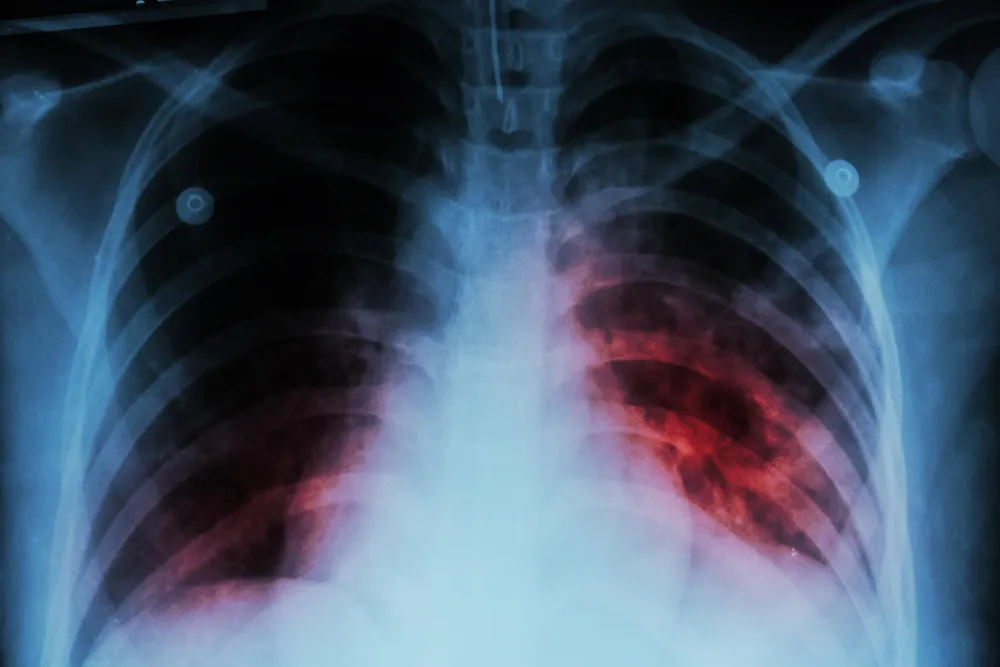

Habrían detectado un caso positivo de tuberculosis en un niño de la ciudad de Caleta Olivia.